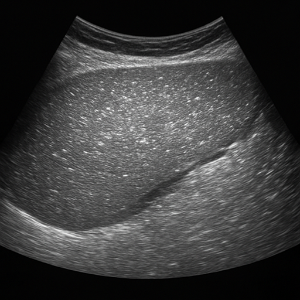

간

간은 복부초음파에서 가장 먼저 살펴보는 장기예요. 초음파로 지방간, 간경변, 결절, 낭종, 혈관종, 간암 등 여러 가지 변화를 감지할 수 있고, 간 기능 검사에 이상이 있을 때 특히 중요하게 확인해요.

정상 소견과 비정상 소견

복부초음파에서 정상 소견은 “언리마커블(unremarkable)” 또는 “특이 소견 없음” 같은 표현으로 나타나요. 예를 들어 간, 췌장, 비장, 신장 등이 특별한 이상 없이 보이면 정상으로 간주되죠.

비정상 소견은 장기별 여러 모습으로 드러날 수 있어요. 대표적으로는 간에 종괴나 지방간, 담낭이나 담도에 돌이나 염증, 신장의 수신증(소변이 고이는 현상), 결석, 복수(복강 내 물) 등이 있고, 맹장염이나 충수염, 복강 내 농양, 동맥류도 발견될 수 있어요.